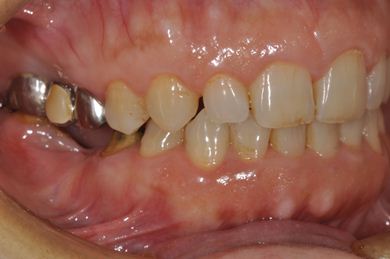

| 性別/年齢 | 女性 / 59歳 | ||||||||||||||||||||||||||||||||

| 主訴 | 奥歯がないので、インプラントか入れ歯の相談をしたい。 | ||||||||||||||||||||||||||||||||

| 治療方針 | 左上奥ソケットリフトにて上顎洞を拳上、骨再生法を行い、インプラント治療を可能にする。 | ||||||||||||||||||||||||||||||||

| 治療内容 | インプラント4本(GBR)、ハイブリッドセラミック4本 | ||||||||||||||||||||||||||||||||

| 総治療費 | 1,680,000円 | ||||||||||||||||||||||||||||||||

| 治療期間 | 11ヶ月 |